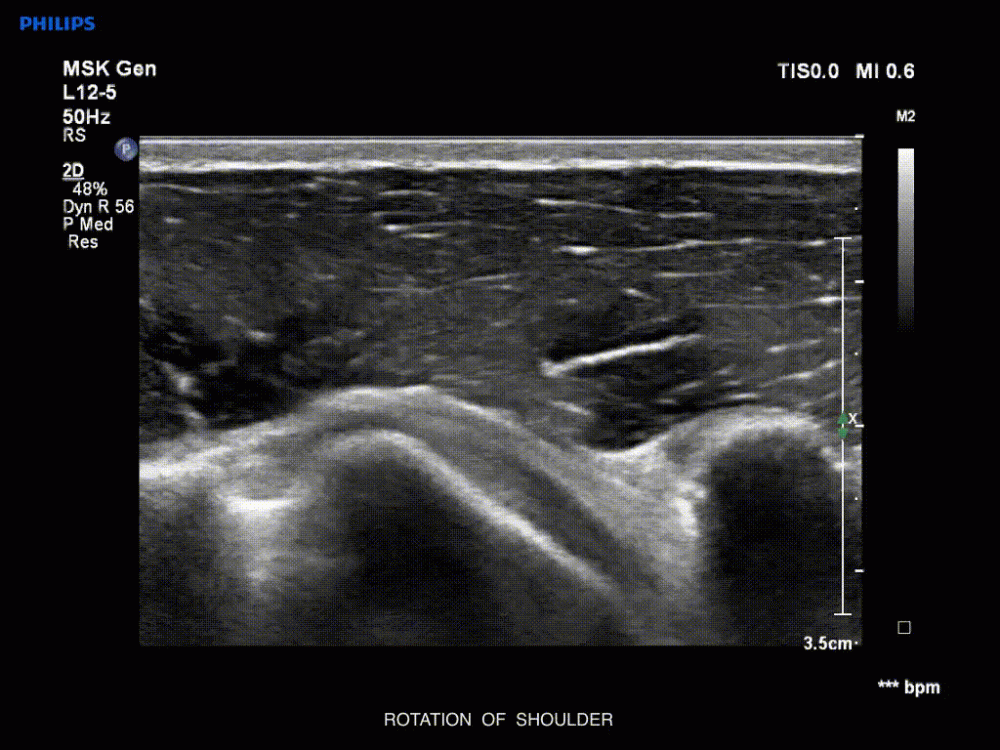

The curriculum of the pain medicine course should be comprehensive and well-structured. Ensure it covers a range of relevant topics, from fundamental pain management principles to advanced techniques like interventional pain procedures and musculoskeletal (MSK) ultrasound. If the course provides practical training in key procedures, this will also enhance its value.

Review the learning objectives to make sure they align with your career goals. For instance, if you’re interested in interventional pain procedures, confirm that the course includes modules on these techniques. Some courses offer specialized tracks, allowing you to focus on specific areas such as MSK ultrasound or pharmacologic pain management.